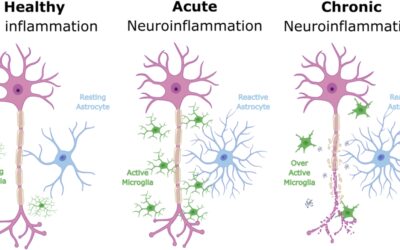

- A first-in-class “synaptic regenerative” small molecule; as a once-daily oral pill. Designed to restore and protect synapses